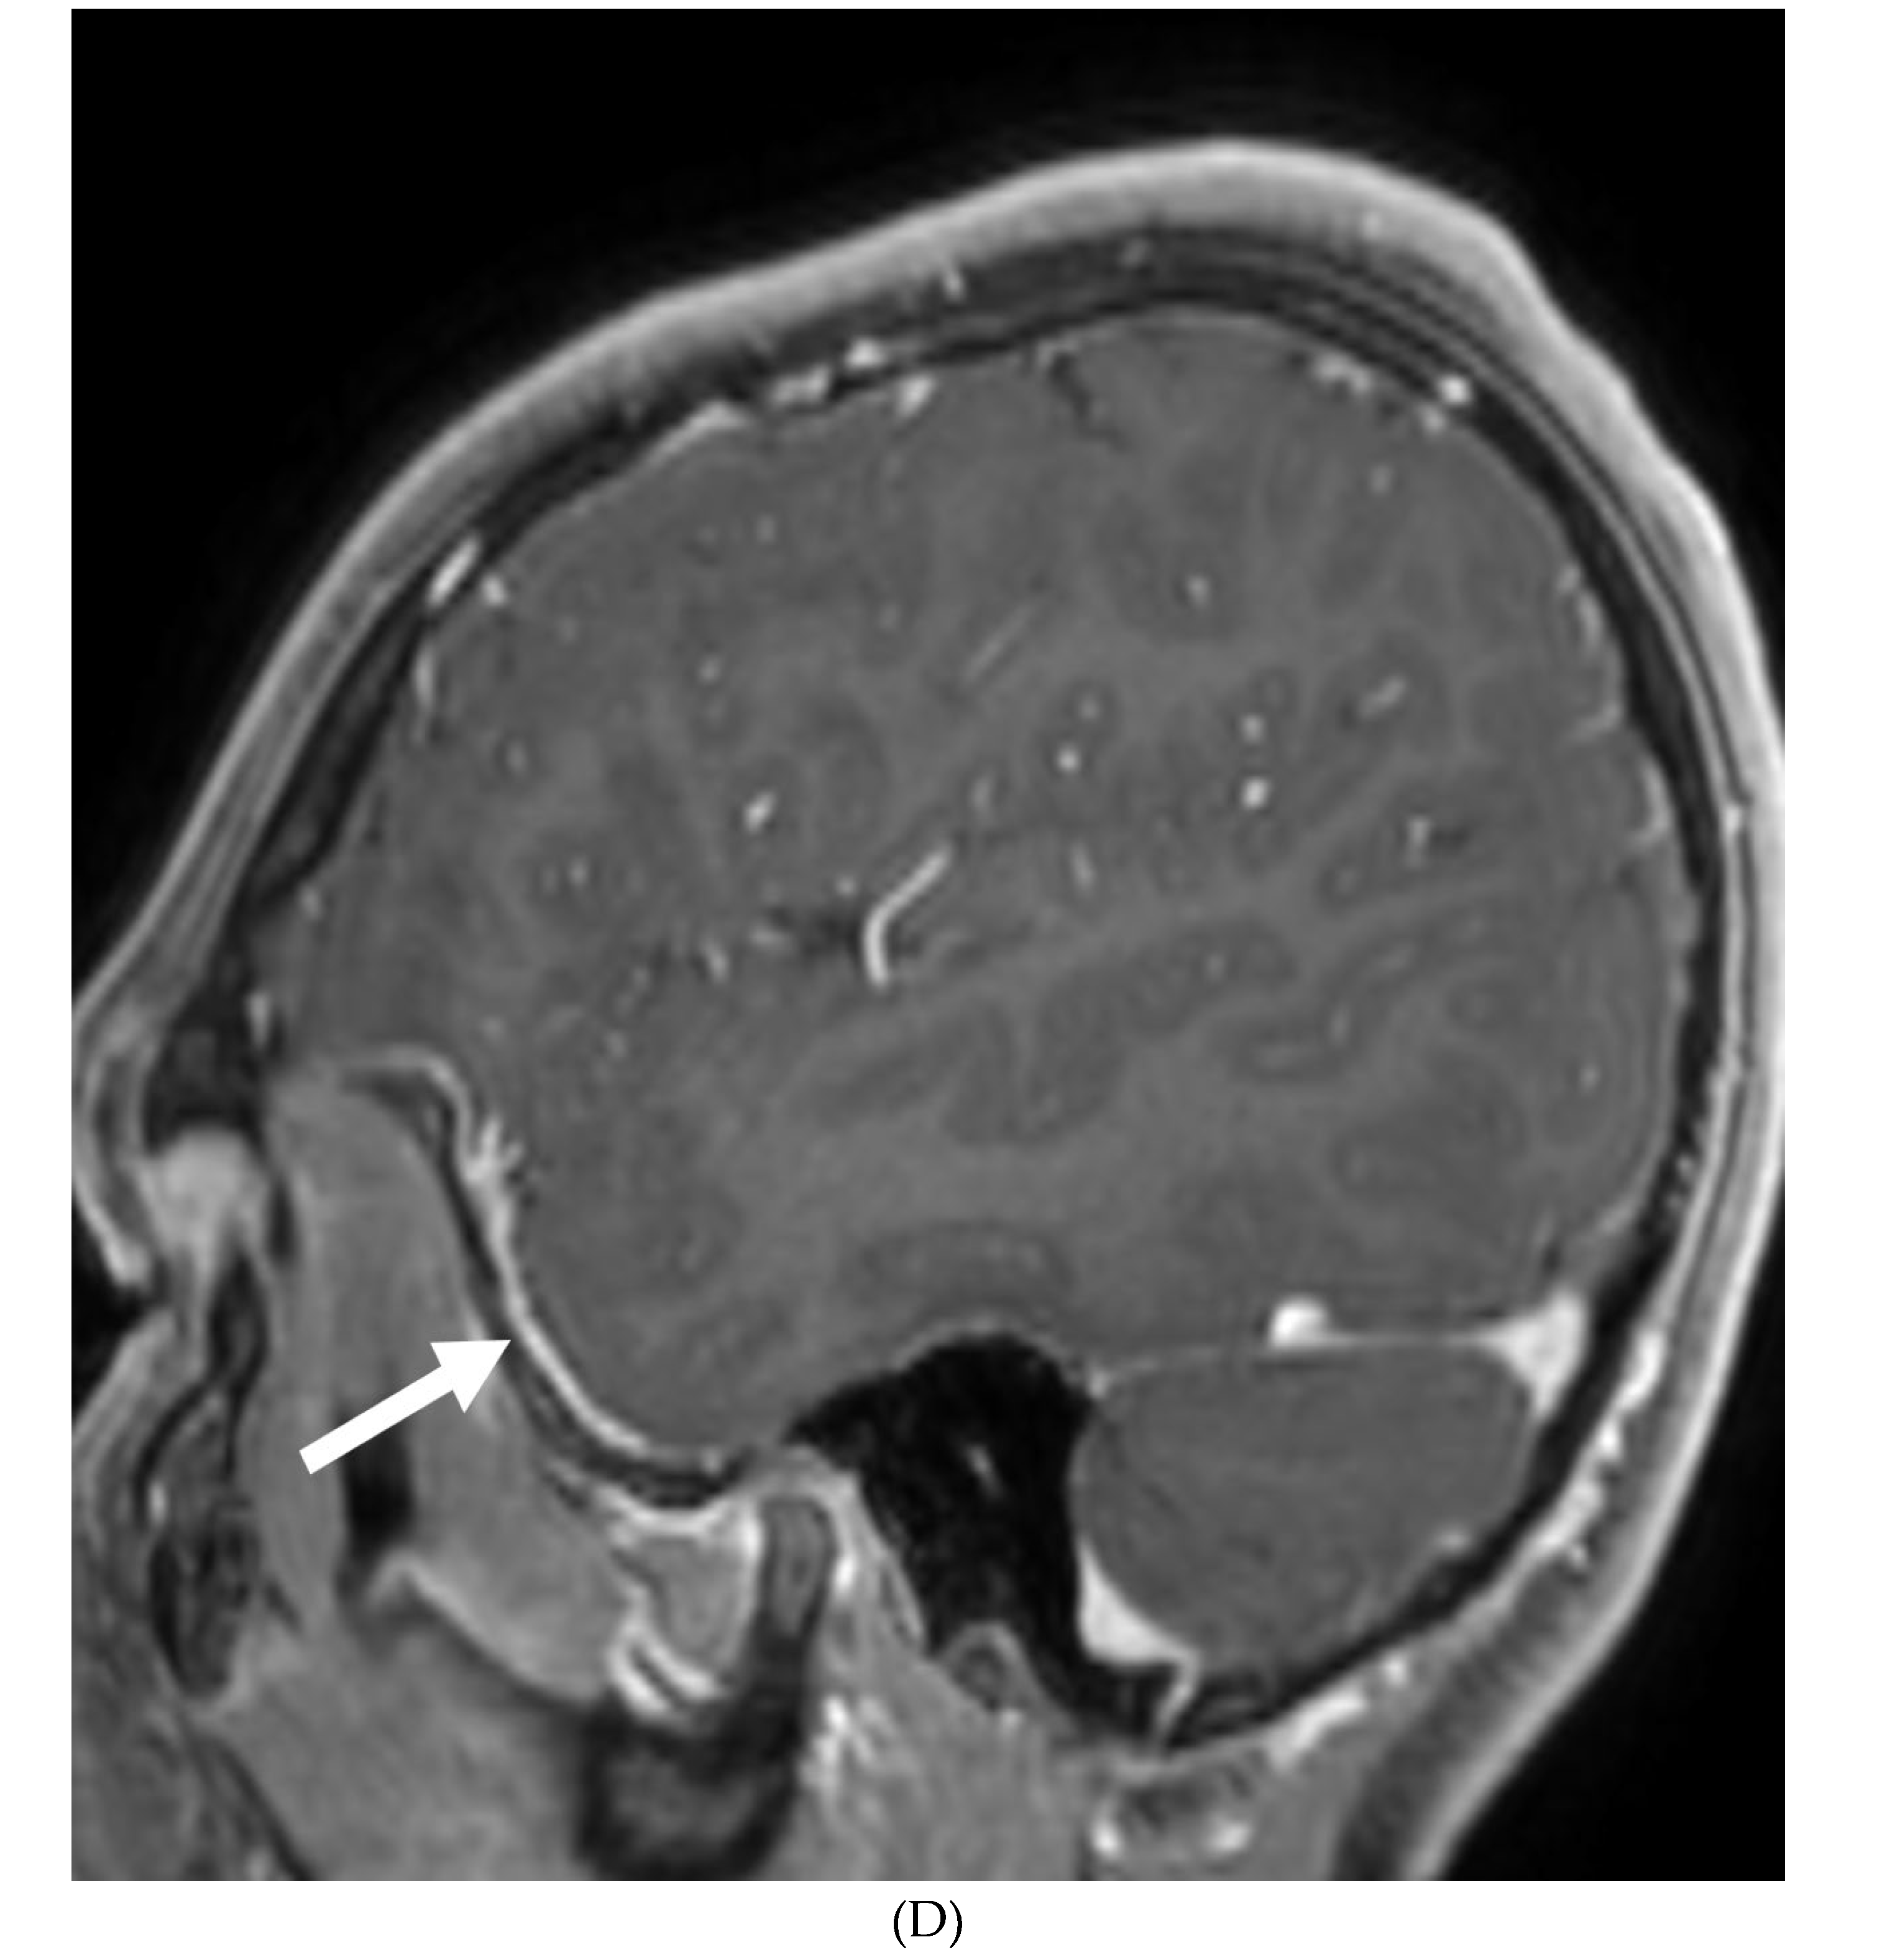

INTRACRANIAL HYPOTENSION (IH)

- Peterson EE, Riley BL, Windsor RB. Pediatric Intracranial Hypotension and Post-Dural Puncture Headache. Semin Pediatr Neurol. 2021 Dec;40:100927. Epub 2021 Sep 3. PMID: 34749914. [CrossRef]

- Schievink WI, Maya MM, Louy C, Moser FG, Sloninsky L. Spontaneous intracranial hypotension in childhood and adolescence. J Pediatr. 2013 Aug;163(2):504-10. Epub 2013 Feb 28. PMID: 23453548. [CrossRef]

- Shah LM, McLean LA, Heilbrun ME, Salzman KL. Intracranial hypotension: improved MRI detection with diagnostic intracranial angles. AJR Am J Roentgenol. 2013 Feb;200(2):400-7. PMID: 23345364. [CrossRef]

- Yuh EL, Dillon WP. Intracranial hypotension and intracranial hypertension. Neuroimaging Clin N Am. 2010 Nov;20(4):597-617. PMID: 20974378. [CrossRef]

- Medina JH, Abrams K, Falcone S, Bhatia RG. Spinal imaging findings in spontaneous intracranial hypotension. AJR Am J Roentgenol. 2010 Aug;195(2):459-64. PMID: 20651205. [CrossRef]